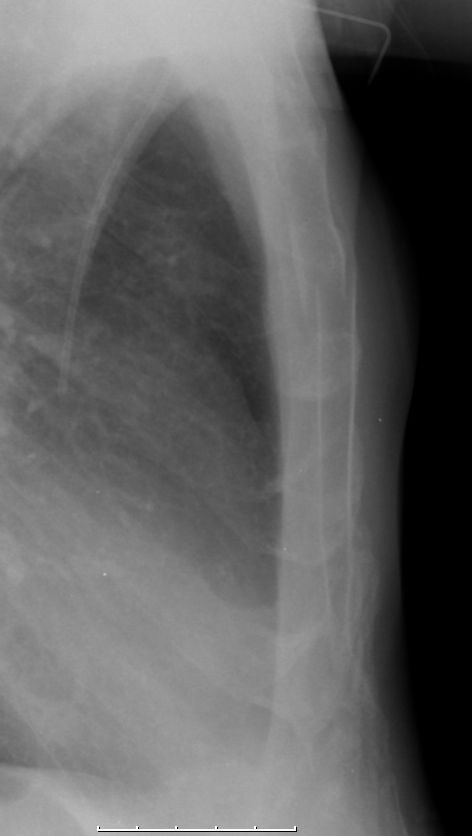

| Fernmetastasen | 48-jähriger Mann, der vor 8 Monaten wegen eines Hypopharynxkarzinoms im Stadium T4a N3 Mo behandelt wurde. Jetzt symptomatische Sternummetastase mit pathologischer Fraktur.![]() |